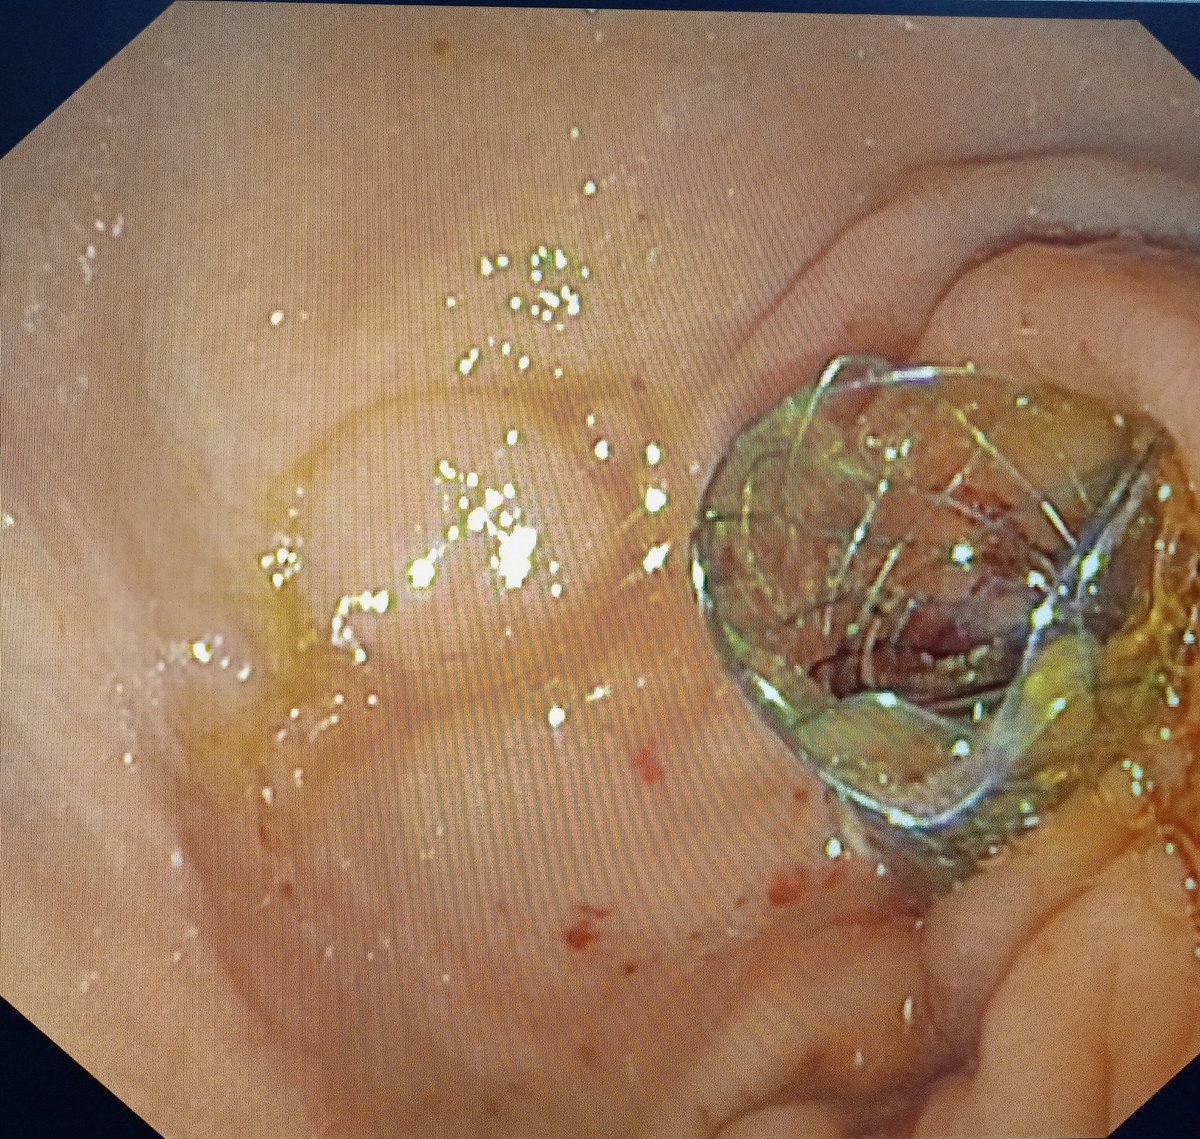

A case of ampullary NET Grade 1 on biopsy Eus/ct/mr suggest lesion limited to ampulla Ampullectomy done. The entire tumor was respected enbloc with intact surrounding capsule There was significant arterial bleeding- controlled with hemoclip application #AIIMSJodhpur